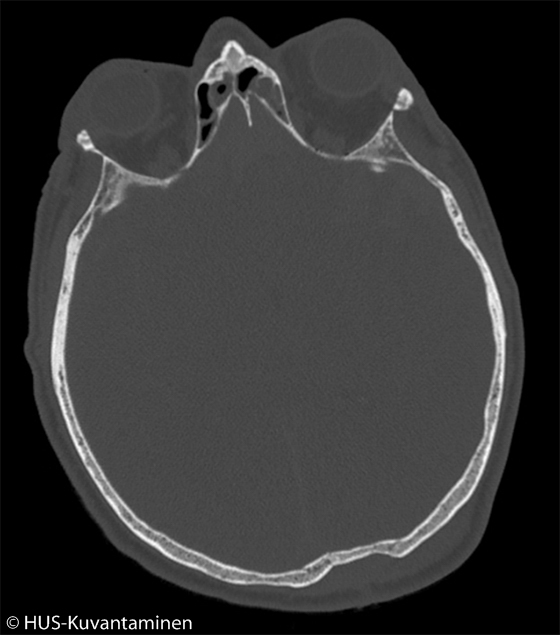

Kallonmurtuma pään TT-kuvassa (kuva 1 ilman löydösmerkintöjä)

Mies löi kaatuessaan päänsä katukiveykseen ja menetti muistinsa useaksi tunniksi.